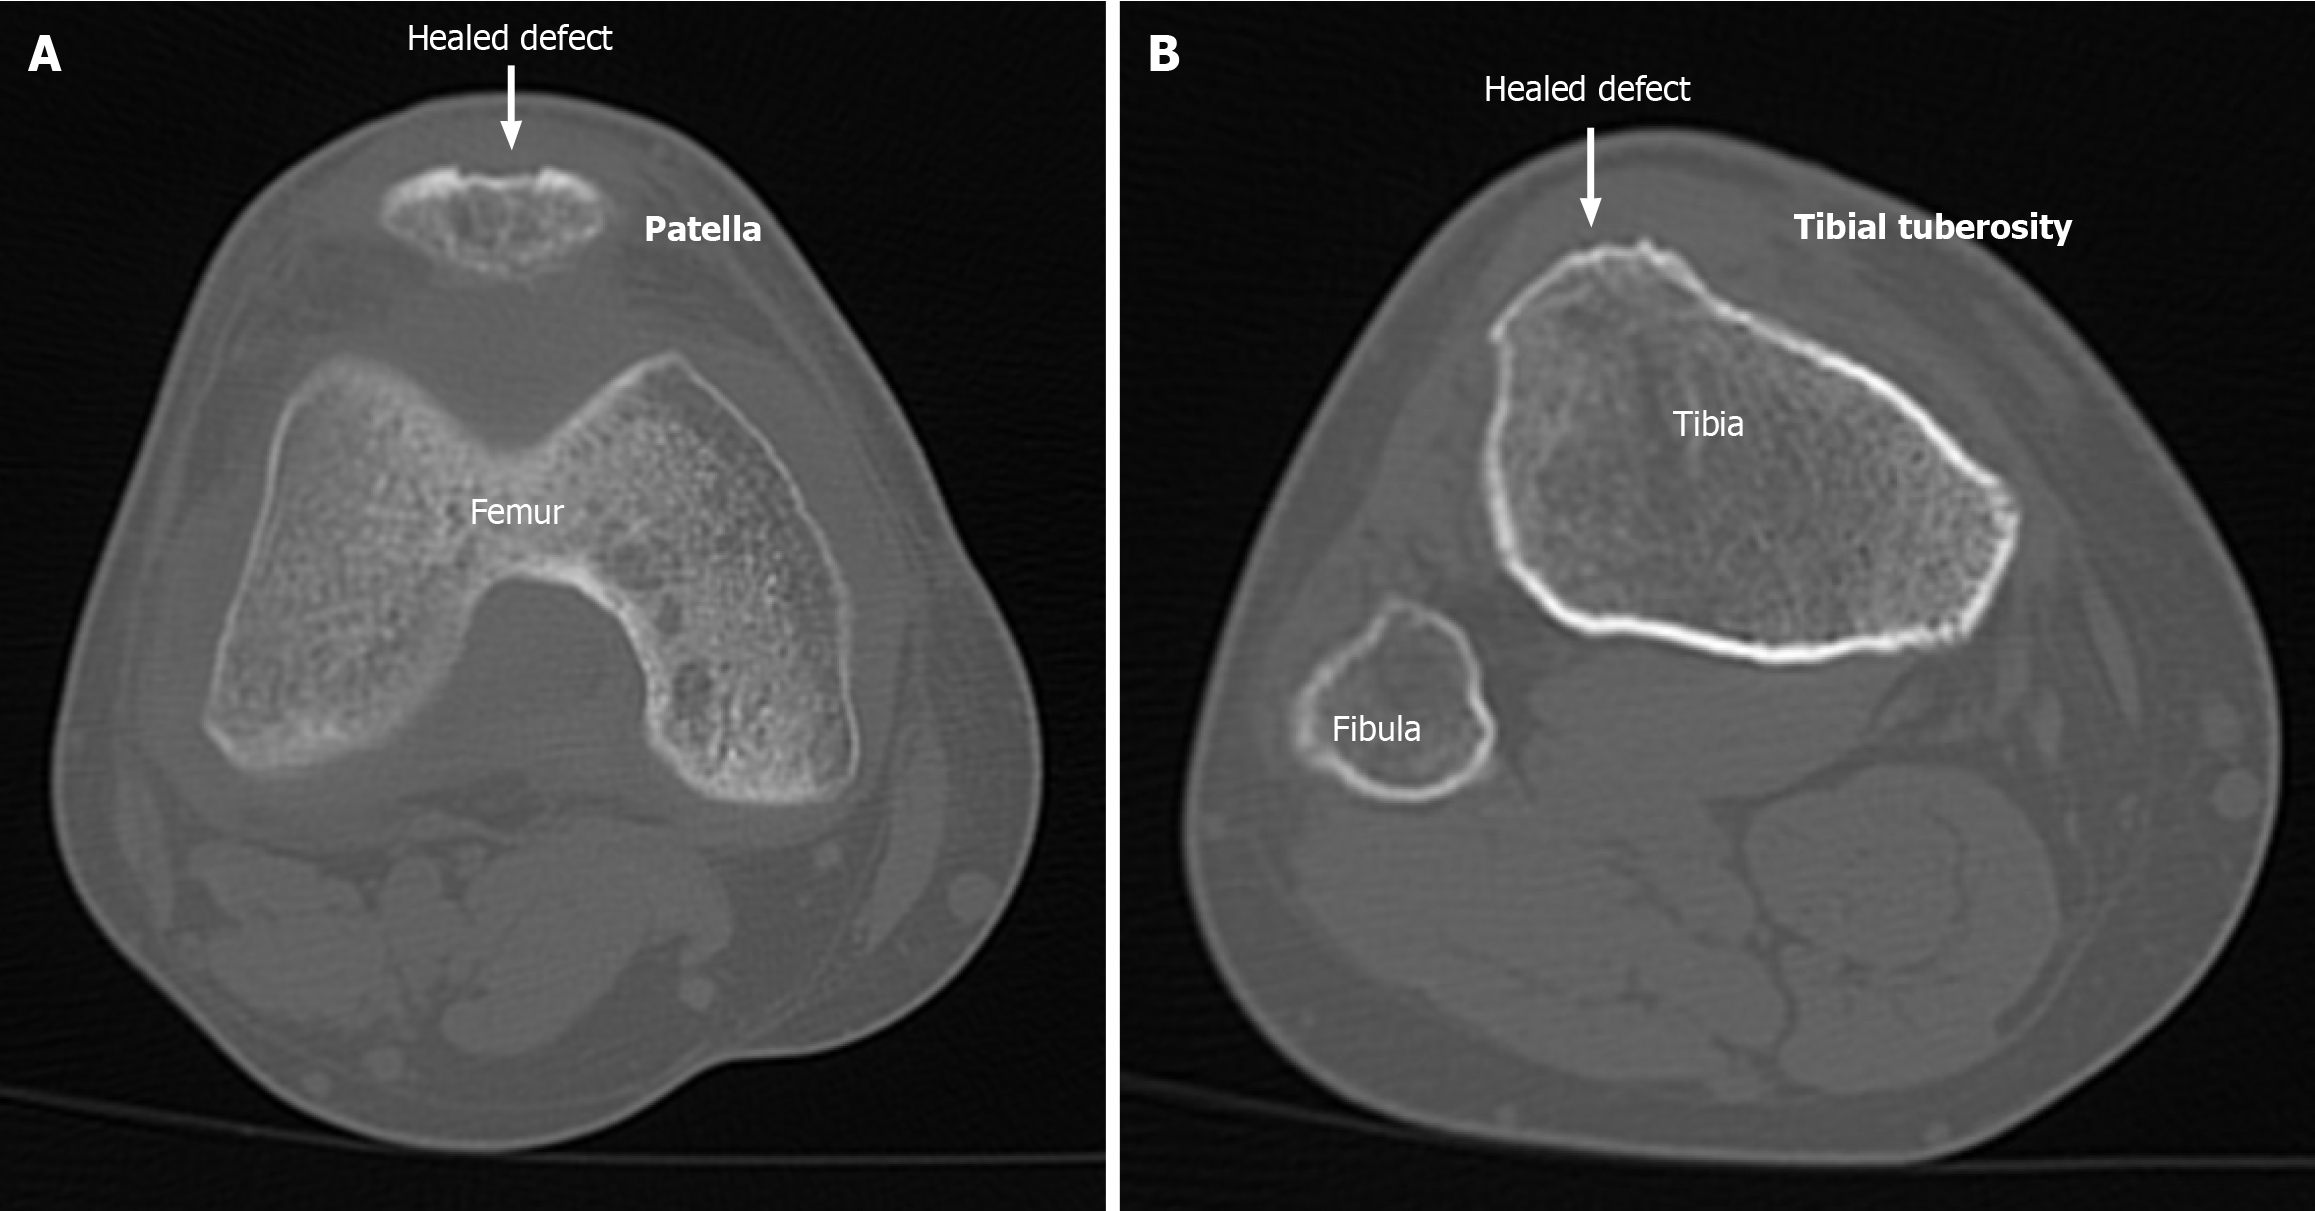

Figure 1 Axial non-contrast computed tomography cuts showing healed patellar and tibial tuberosity donor sites in a patient after 1 year.

A: Patellar site; B: Tibial Tuberosity site.